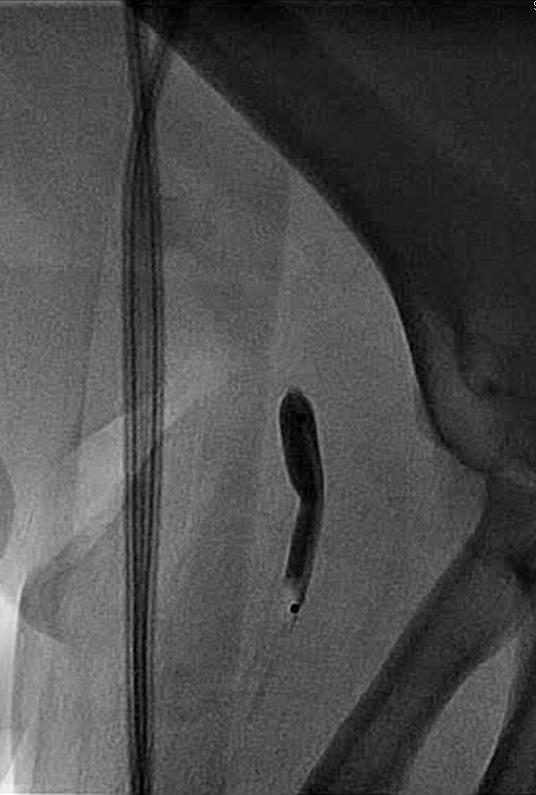

A 6F 65 cm sheath was advanced to the left subclavian artery and a 7 mm diameter 40 mm length balloon was positioned at the lesion over a 0.035 inch J-tip wire. The balloon was inflated to 8 atmospheres for thirty seconds:

At this point, the balloon would not deflate and could not be retracted into the sheath. Attempts to aspirate and dilute the contrast in the balloon were unsuccessful. Though a wire was passed around the balloon, it could not be snared. After some deliberation, it was decided to pull the balloon back to the brachial artery (Figure 3):

Under ultrasound guidance, a micropuncture needle was advanced into the mid-body of the balloon. Aspiration of the needle did not yield blood or contrast material, though on fluoroscopy the balloon appeared deflated and was then able to be pulled back into the sheath. Final angiograms showed mild spasm in the brachial artery without apparent arterial injury and the patient had an uneventful recovery. This event was reported to the manufacturer, which promptly initiated a recall of this balloon from its product line.